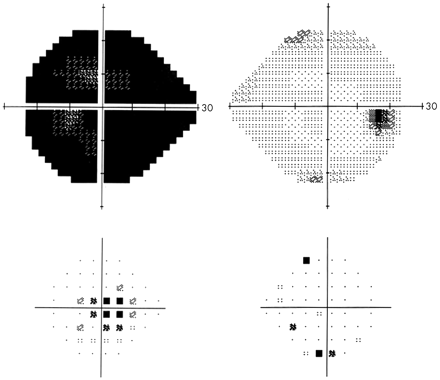

既往高脂血症多年。戒烟20年。视力:右眼20/20,左眼数指。右眼能识别9/12色板,左眼为0/12。左眼有传入性瞳孔阻滞。右眼视盘有先天异常,左眼视盘苍白水肿。左眼下方视野有弧形缺损。

图1 第二次手术后Humphrey自动视野检查及左眼的视力丧失